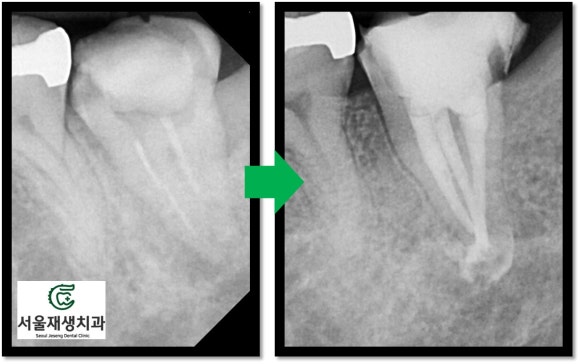

뿌리 측면에 녹아있던 뼈가 재생되었습니다.

불과 치료 두 달만의 일입니다.

뿌리끝까지 꼼꼼하게 약제를 채워넣고,

치아의 머리도 레진이라는 재료로 충전하여 보강해줍니다.

이제 헬멧(=크라운)을 씌워 머리를 보호해주면 치료는 종료됩니다.

총 3개월 정도 소요된 치료였습니다.